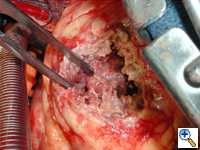

An anterolateral left ventriculotomy is made through the area of infarction parallel to and two centimeters away from the left anterior descending artery. Stay sutures can be placed through the edges of the ventriculotomy to maintain an open visual field. The interventricular septum, area of infarction, and site of rupture are visualized (Figure 3).

The necrotic portion of the septum is inspected but no debridement is necessary. The defect is not closed rather it is excluded from the ventricular cavity (Figure 4).